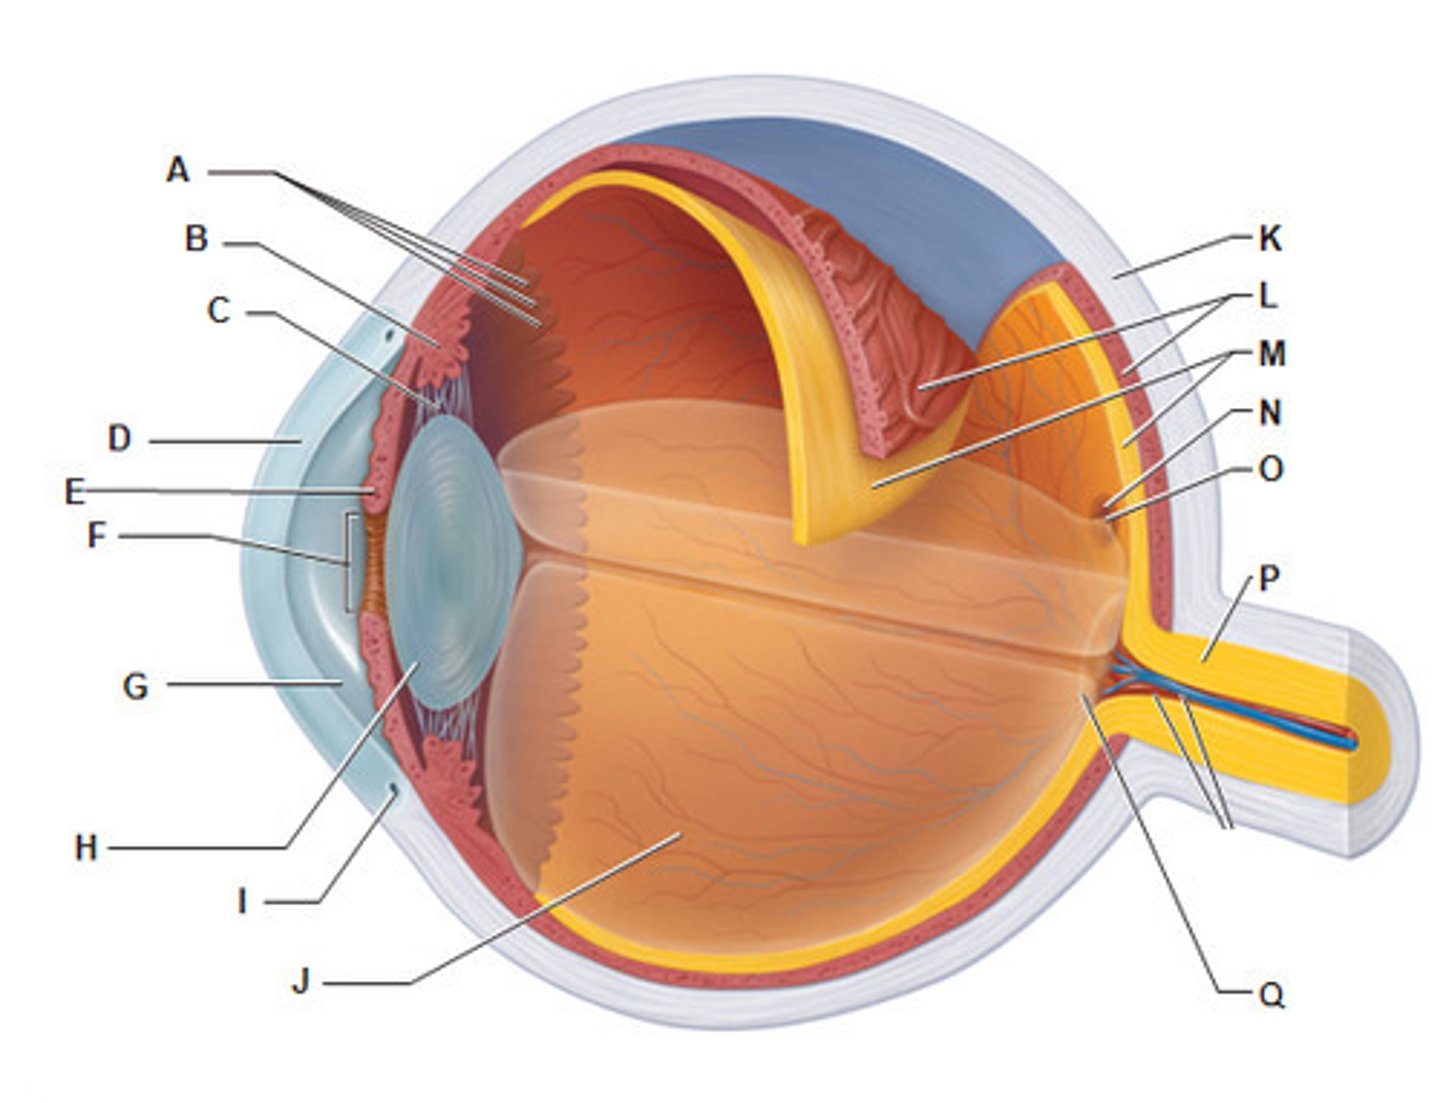

anterior cavity (of eye)

iris

optic disk (blind spot)

choroid

ciliary body

B

ciliary process

conjunctiva

cornea

D

fovea centralis

suspensory ligaments

C

vitreous humor

lens

H

macula lutea

posterior cavity (of eye)

pupil

F

retina

M

sclera

optic nerve